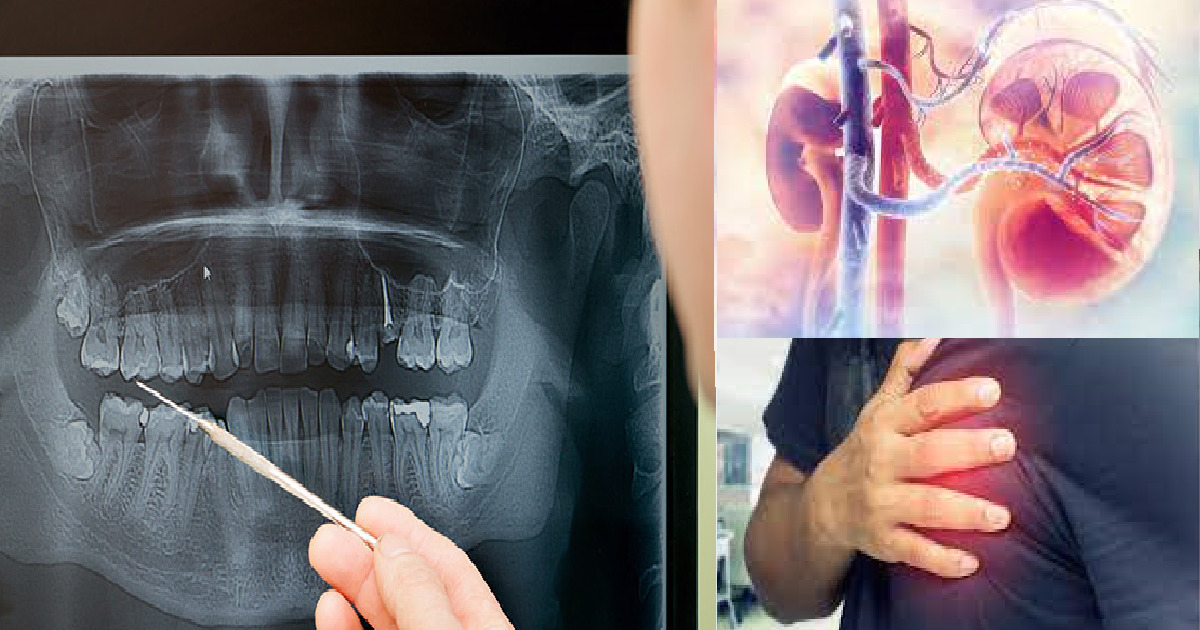

Effects of untreated tooth decay

Untreated dental problems can have far-reaching effects on your health. Many people think that issues in the oral cavity only affect the teeth, but the opposite is true. Here is a list of health problems that can arise:

- Inflamed arteries

- Swollen legs

- Diseases of the heart, kidneys, eyes, or joints